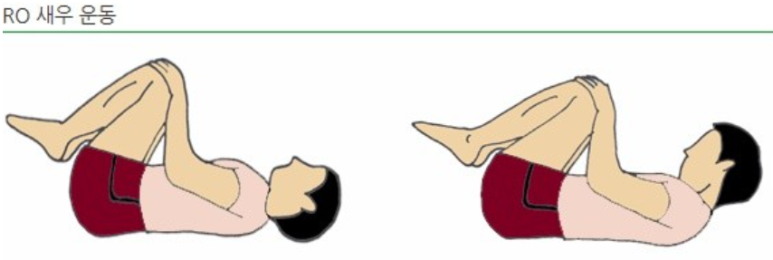

척추후만을 줄이기 위해서 새우운동이 도움됩니다.